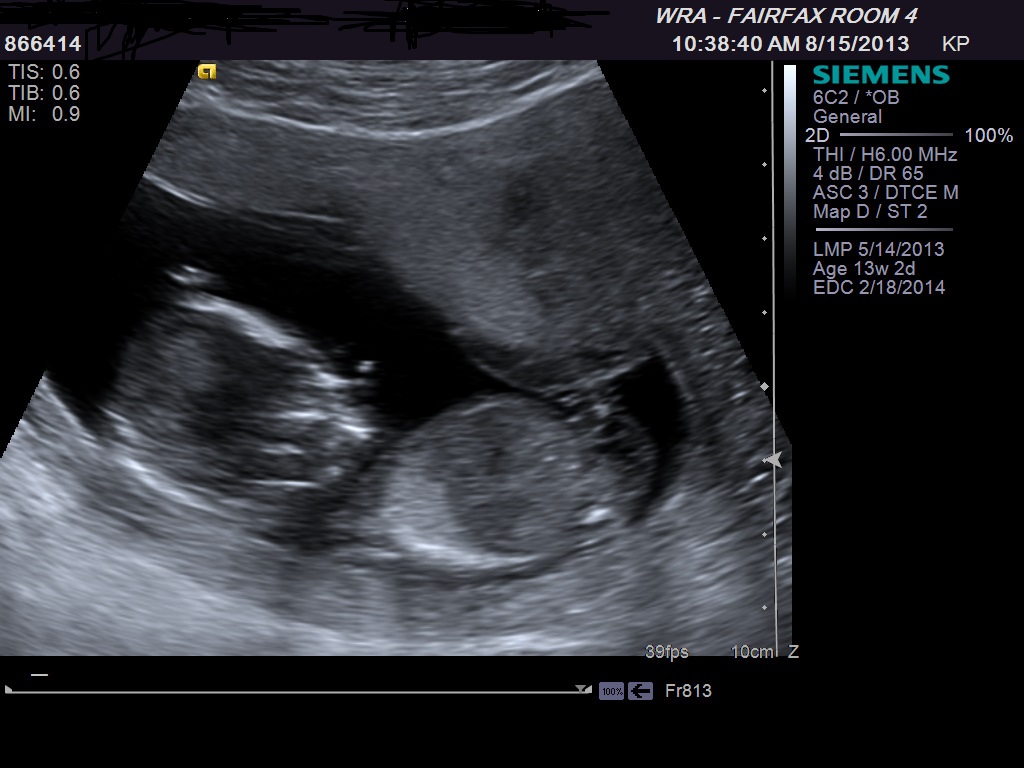

I have to go to library to post my ultrasound, and I cant wait till my nex appt Oct to know if its a boy or Girl. Please Can you guess from ultrasound i am oposting hereAttachment 13979Attachment 13980Attachment 13981